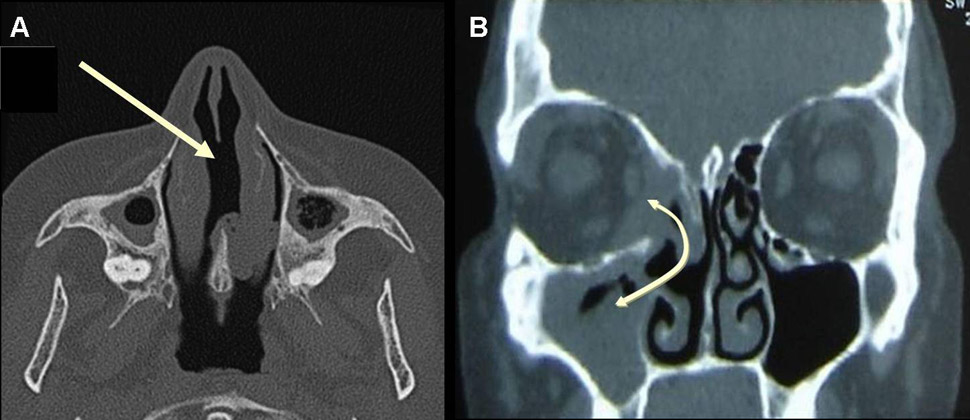

Figure 2

A) CT scan of the sinus in a patient with GPA, showing nasal septum perforation (arrow) and maxillary sinusitis with some degree of maxillary sinusitis and atrophy, with osteosclerosis and bony thickening of the paranasal sinuses. B) CT scan of the sinus in a patient with GPA showing sinusitis and sinus wall erosion leading to the formation of a communication (fistula) between right maxillary sinus, nasal cavity and orbit (double-headed arrow).